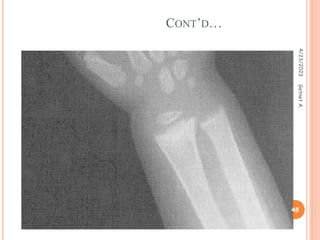

Radiology

 Generalized decrease in the skeletal radiodensity

 Widening, capping and fraying at the end distal of the bones,

best seen at the end of radius and ulna.

CONT’D…